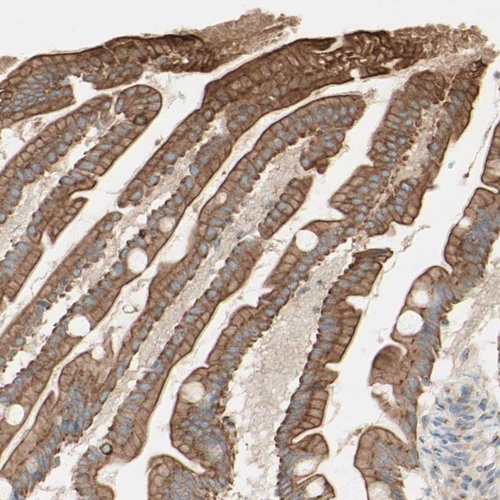

Immunohistochemical staining of human small intestine shows moderate cytoplasmic positivity in glandular cells.